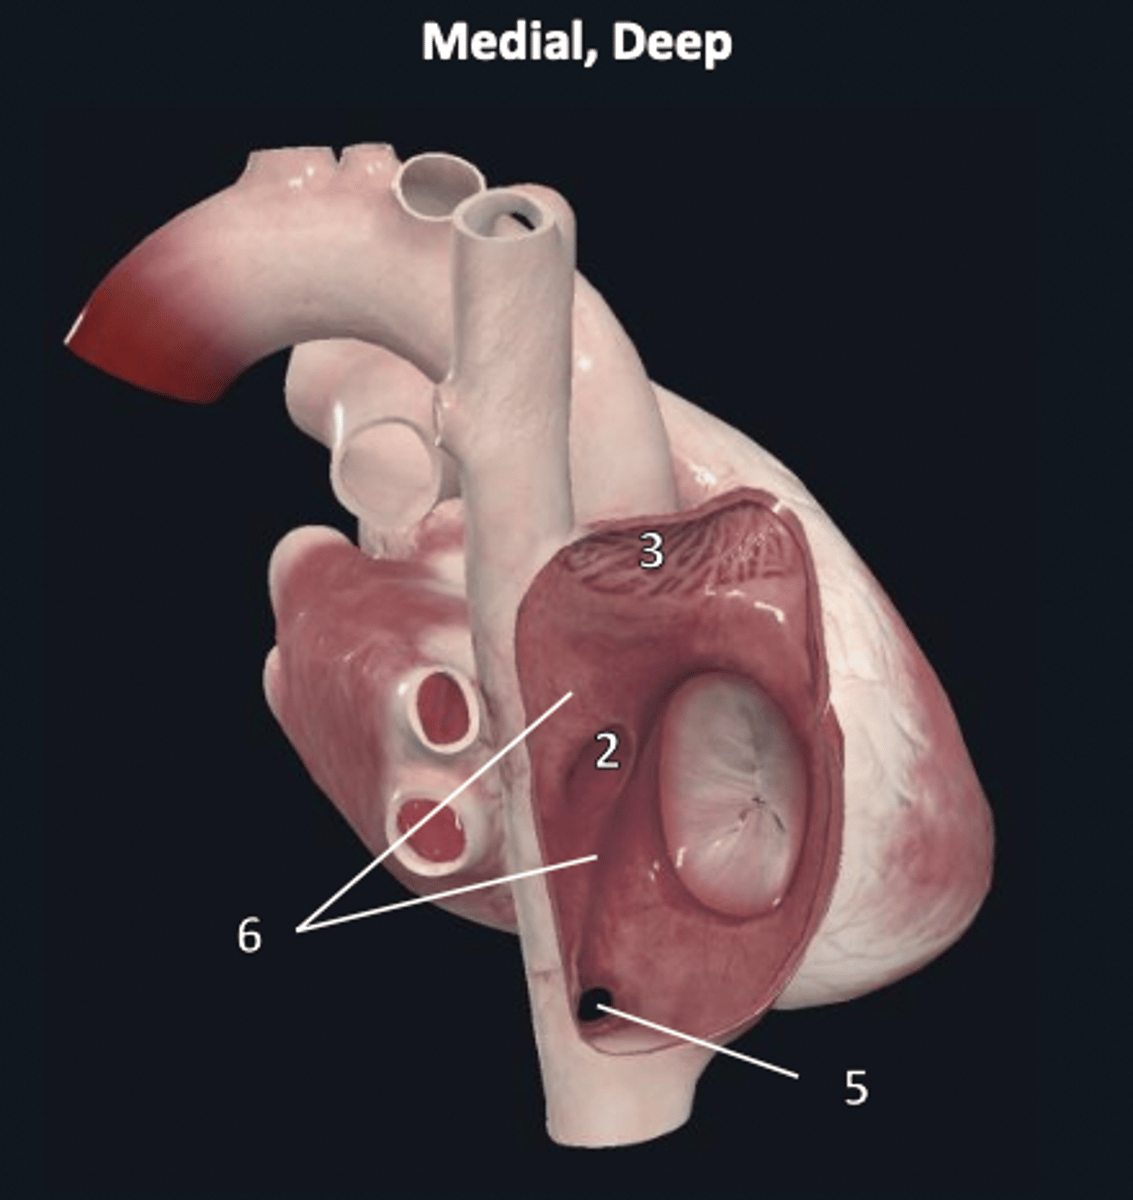

right ventricle

1

trabeculae carneae

2

septal papillary muscle

3

anterior papillary muscle

4

inferior papillary muscle

5

chordae tendineae

6

moderator band

7

tricuspid valve

8

pulmonary semilunar valve

9

interventricular septum

10